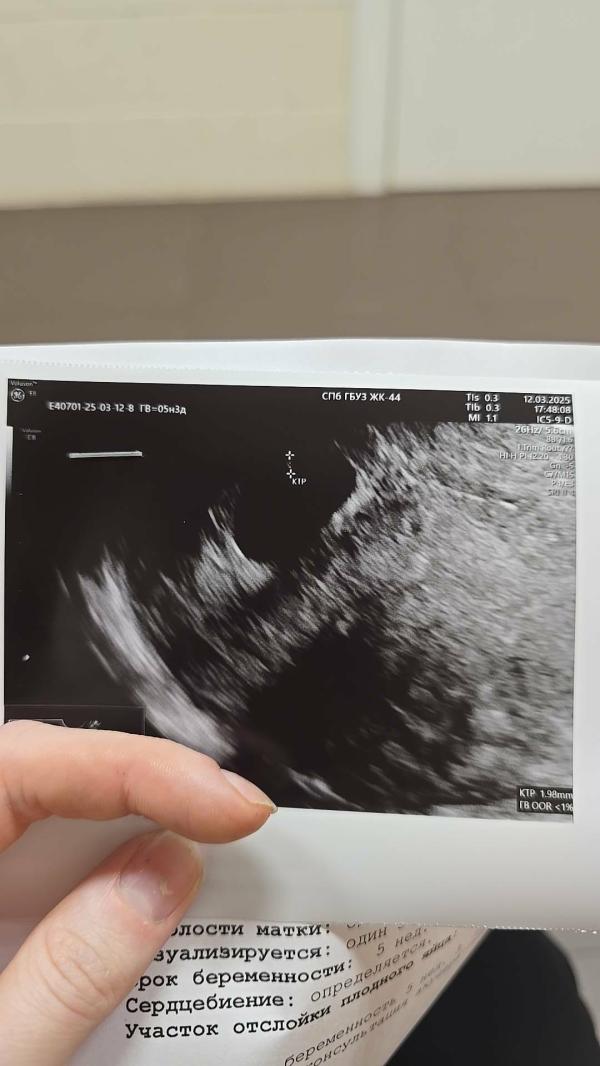

ну чтож, вести с узи. Поставили ровно 5 недель вместо 5.4 по месячным. Измерили креветку, 1.98 мм. Где то прикрепилась крайне в углу, что до нее датчиком еле как достали😂 Ну в целом сказали все хорошо прикреплено, размерам соответствует, сердечко стучит ♥️🙏 Сказали что если ничего не будет беспокоить, то следующий раз уже скрининг. А я думаю, не страшно же будет если я схожу в 10-ых числах следующего месяца, для спокойствия проверить просто?